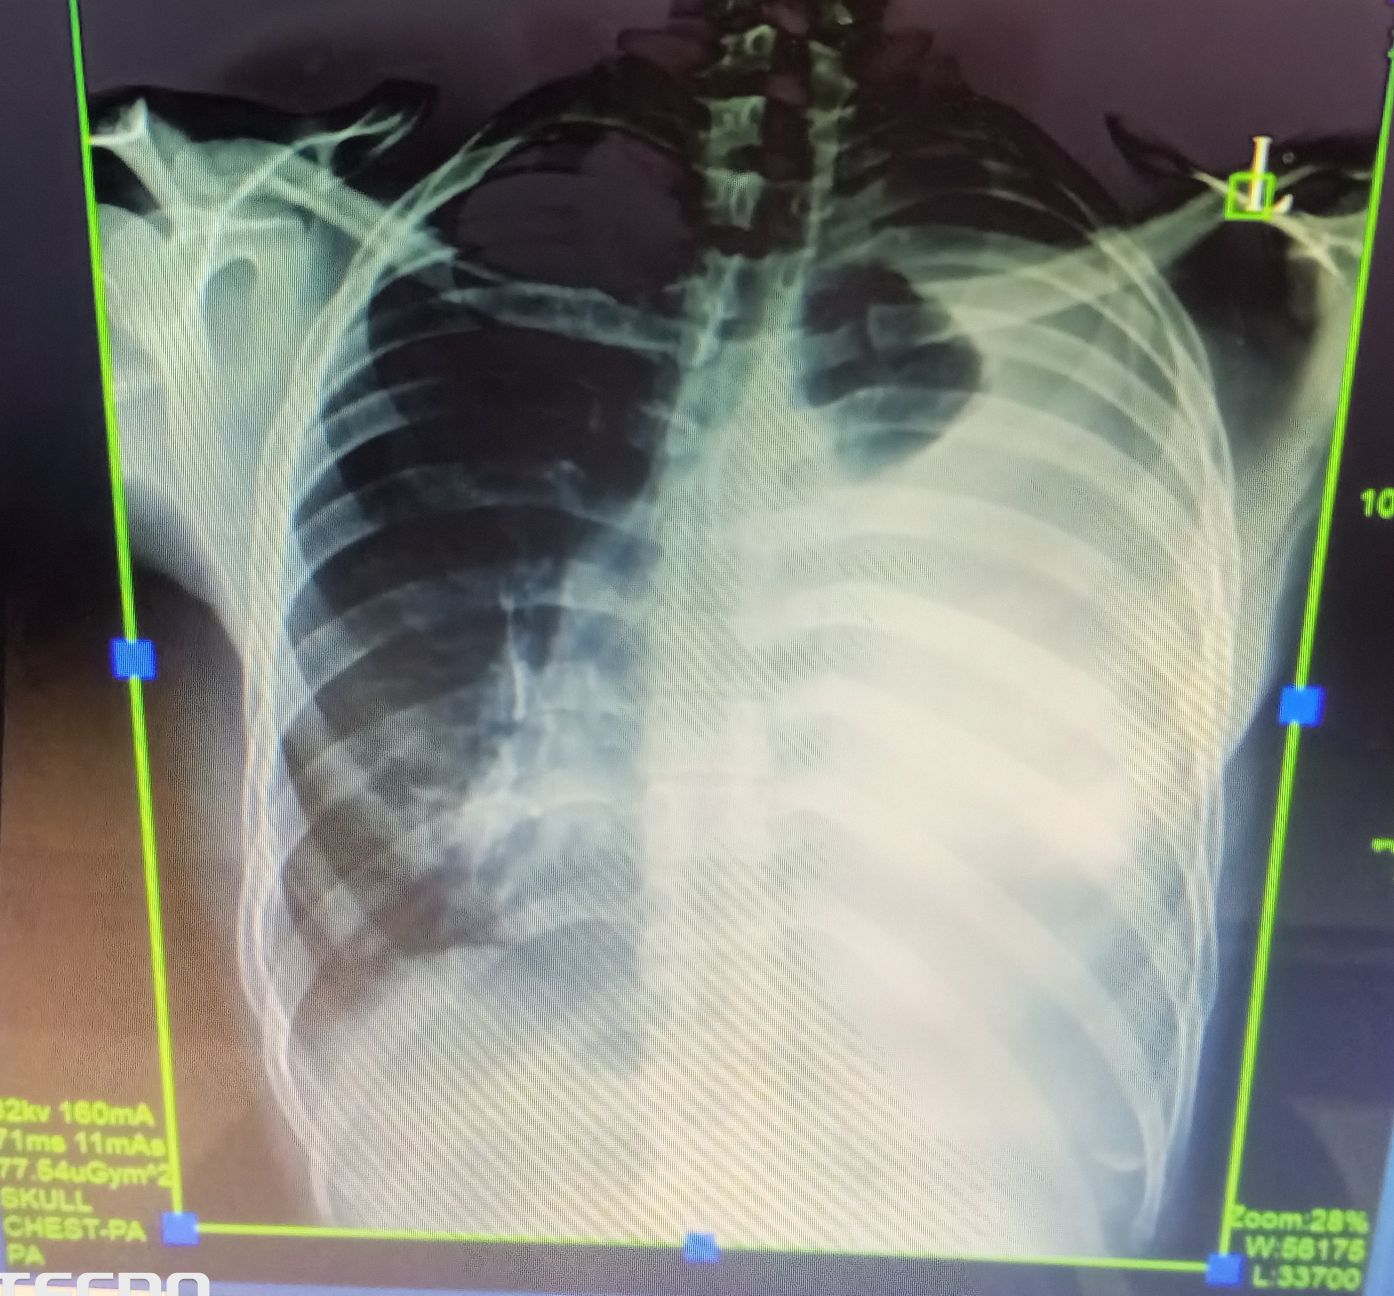

Pulmonology

Pleuraleffusion